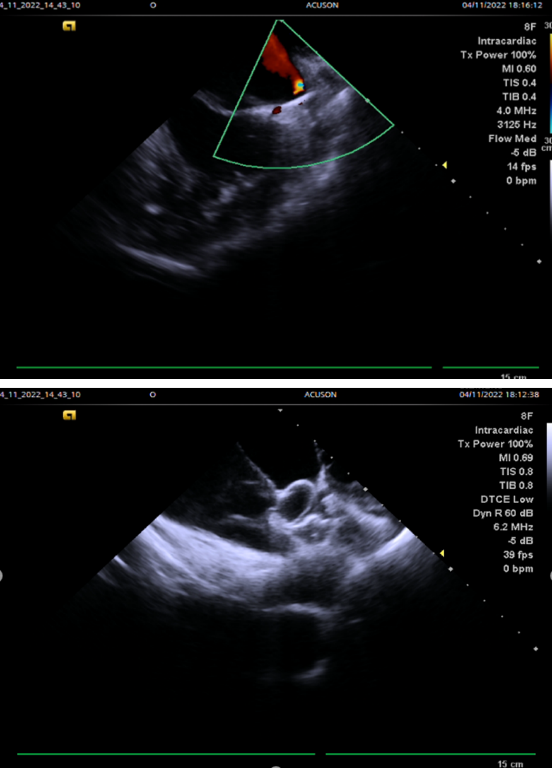

术中经8FR心腔内超声导管引导穿刺房间隔后,多切面测量左心耳尺寸大小,为封堵器的选取提供参考。

术后即刻应用8FR 心腔内超声评估封堵效果,密封盘完全封堵且不影响二尖瓣和左上肺静脉血流,心腔内超声下观察牵拉实验,固定盘稳定无移位。